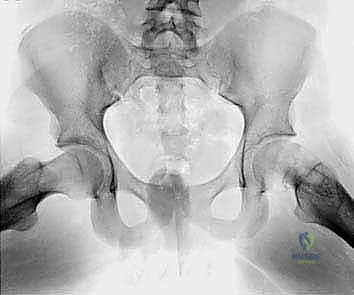

التشخيص الإشعاعي الدقيق: رؤية ما وراء الألم

لا يمكن اتخاذ قرار بإجراء عملية كبرى مثل قطع العظم الانثنائي بين المدورين دون تقييم إشعاعي دقيق وشامل.

- الأشعة السينية العادية (X-rays):

- تُطلب بوضعيات محددة: أمامي خلفي (AP) ووضعية الضفدع (Frog-leg lateral).

- علامة كلاين (Klein's Line): في الأشعة الأمامية، يجب أن يتقاطع الخط المرسوم على الحافة العلوية لعنق الفخذ مع جزء من رأس الفخذ. في حالة الانزلاق، لا يتقاطع هذا الخط مع الرأس، مما يؤكد التشخيص.